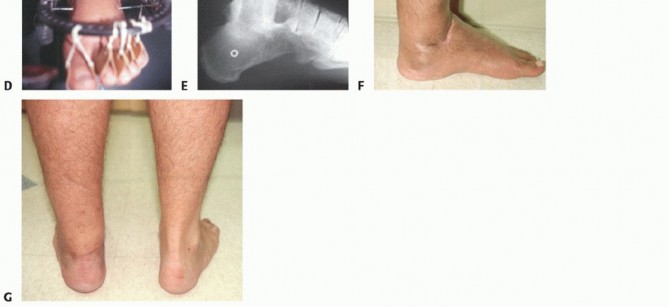

- The arthrodesis must be in a plantar neutral position. A fusion with the foot in equinus will severely compromise the functional outcome (FIG 4).

- FIG 4 • A. Tibiocalcaneal arthrodesis with loss of talar head and navicular in crush injury of foot. B. Full lateral x-ray of tibia and foot is accurate method to evaluate foot position. With no ankle motion and compromised forefoot motion, aligning the foot in plantar neutral position and correct forefoot rotation is

essential for a functional result. Observe mature proximal bone transport to equalize leg length.